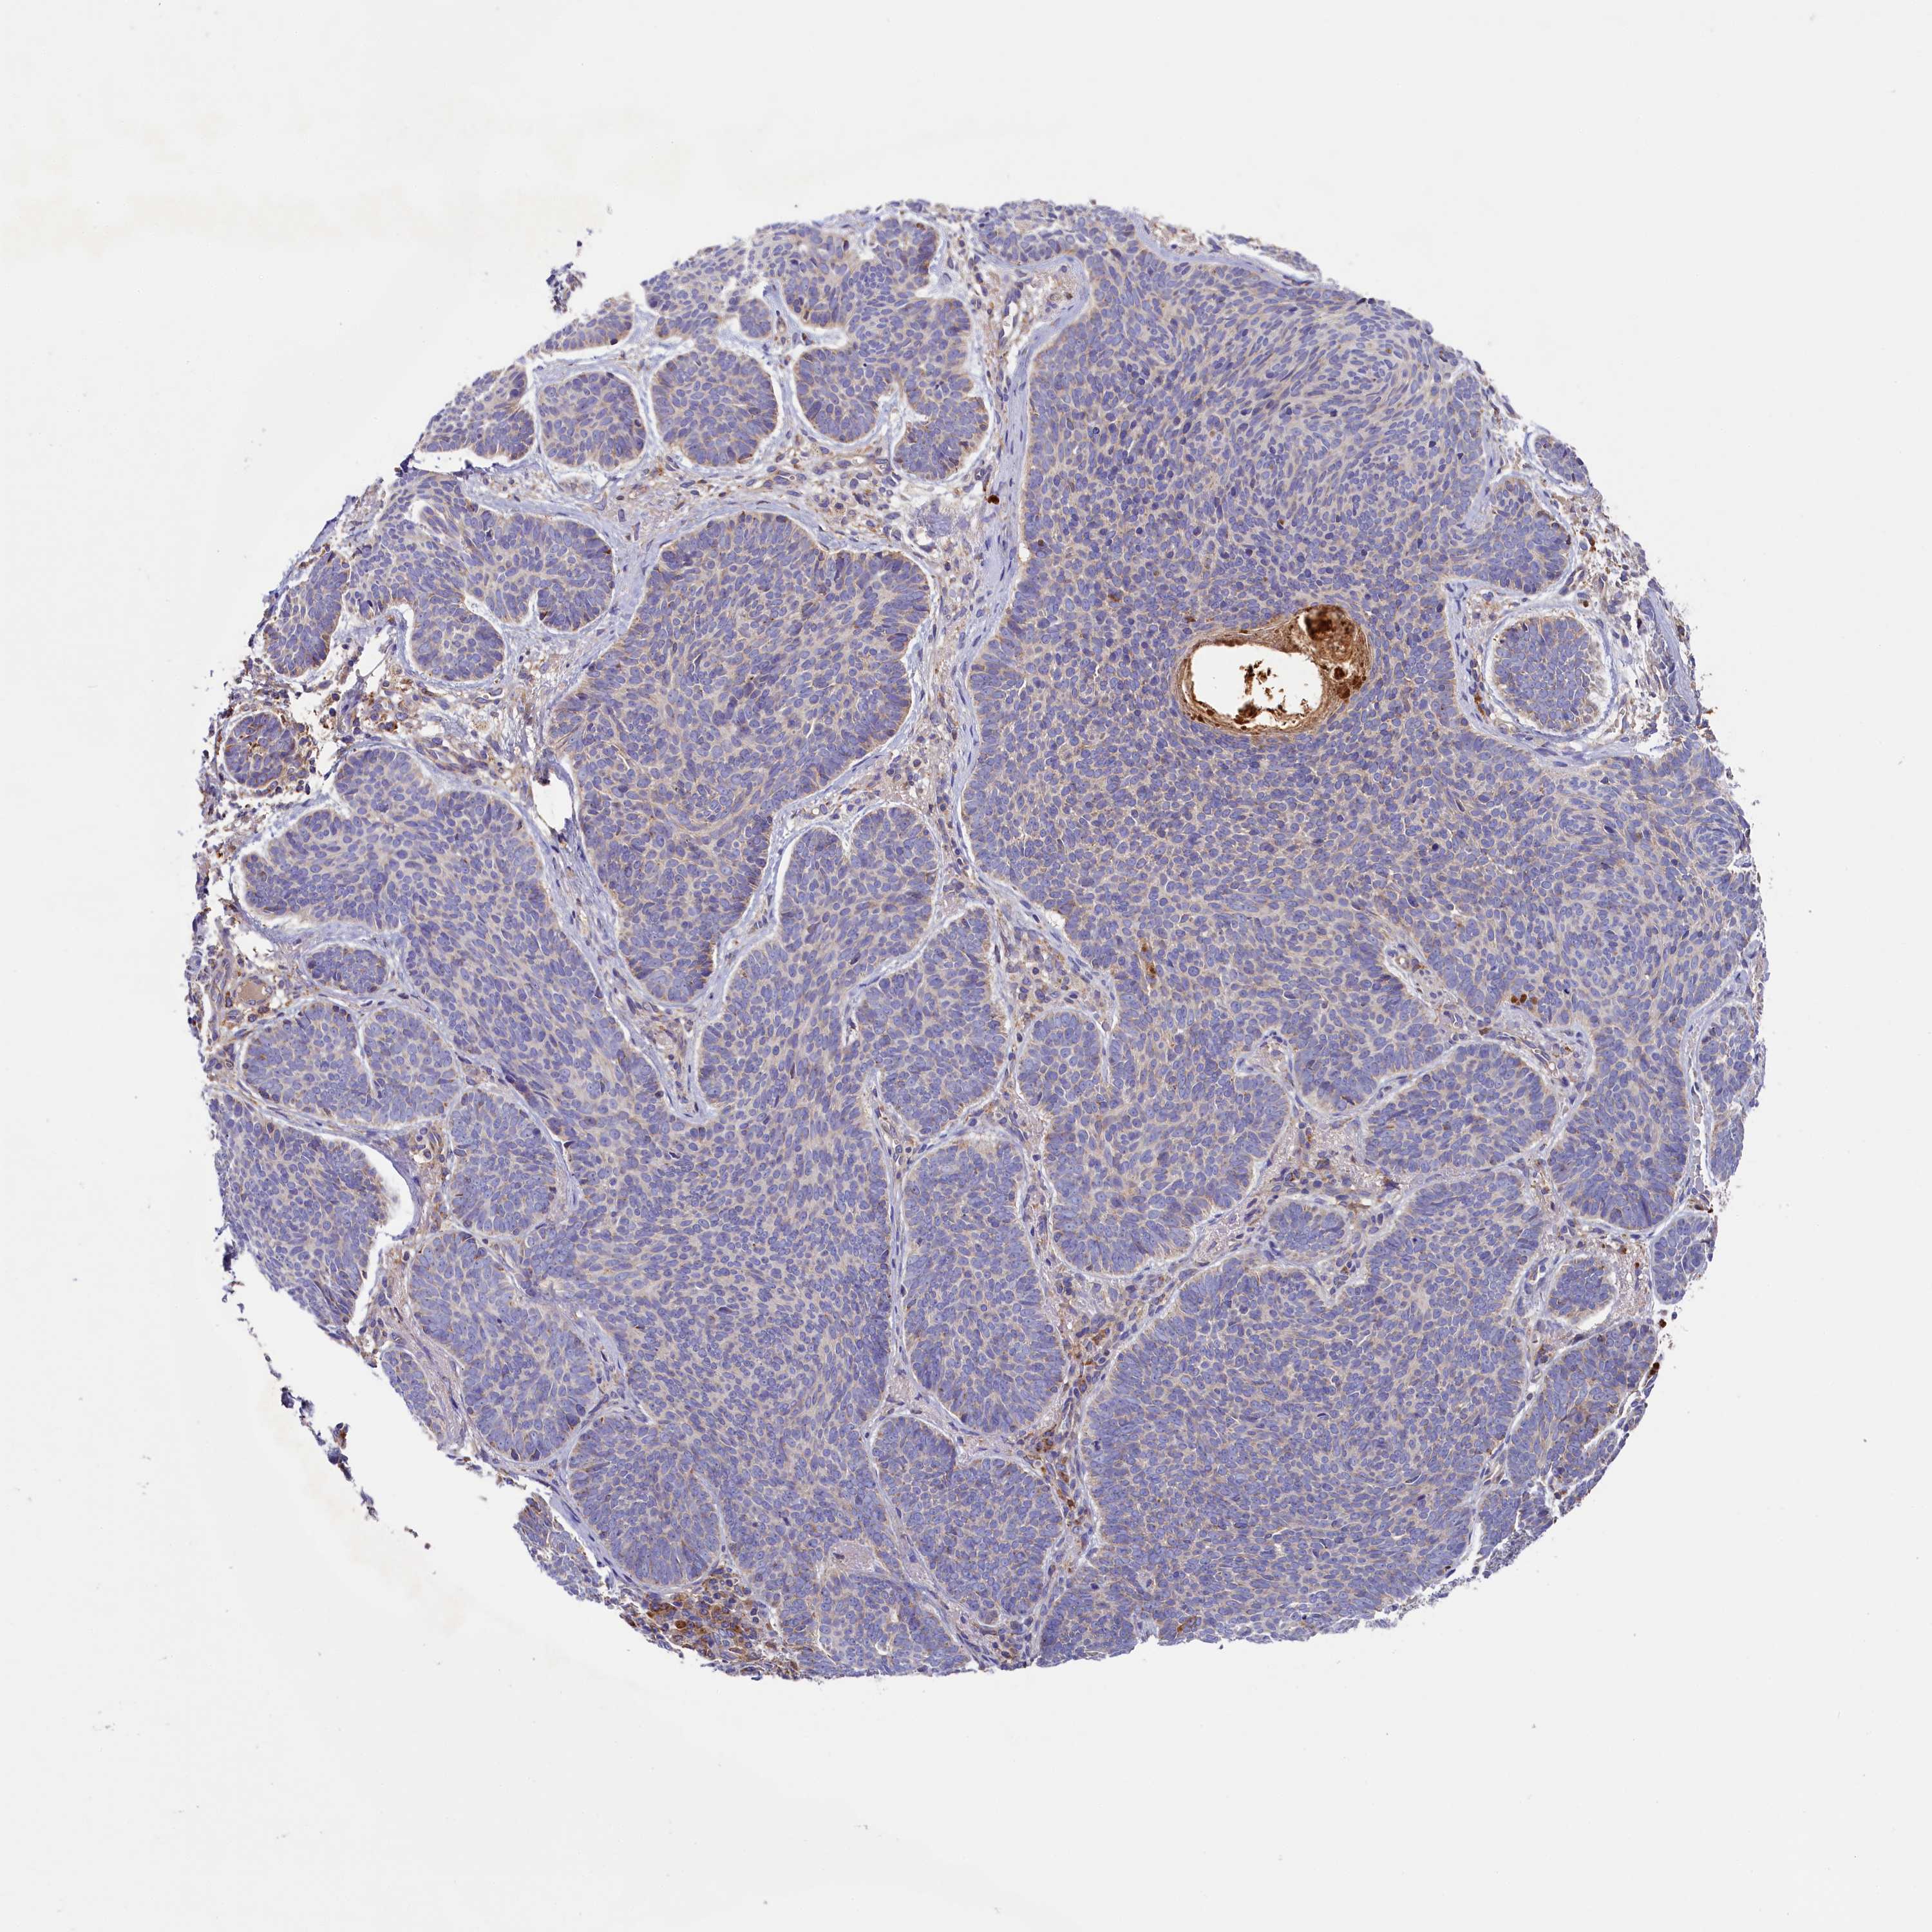

SKIN CANCER - Protein expressioni

A mouse-over function shows sample information and annotation data. Click on an image to view it in a full screen mode. Samples can be filtered based on level of antibody staining by selecting one or several of the following categories: high, medium, low and not detected. The assay and annotation is described here.

Antibody staining in the annotated cell types in the current human tissue is reported as not detected, low, medium, or high, based on conventional immunohistochemistry profiling in selected tissues. This score is based on the combination of the staining intensity and fraction of stained cells.

Each image is clickable and will lead to virtual microscopy that enables deeper exploration of all samples and also displays staining intensity scores, fraction scores and subcellular localization as well as patient and tissue information for each sample.

Antibody HPA035882

Basal cell carcinoma